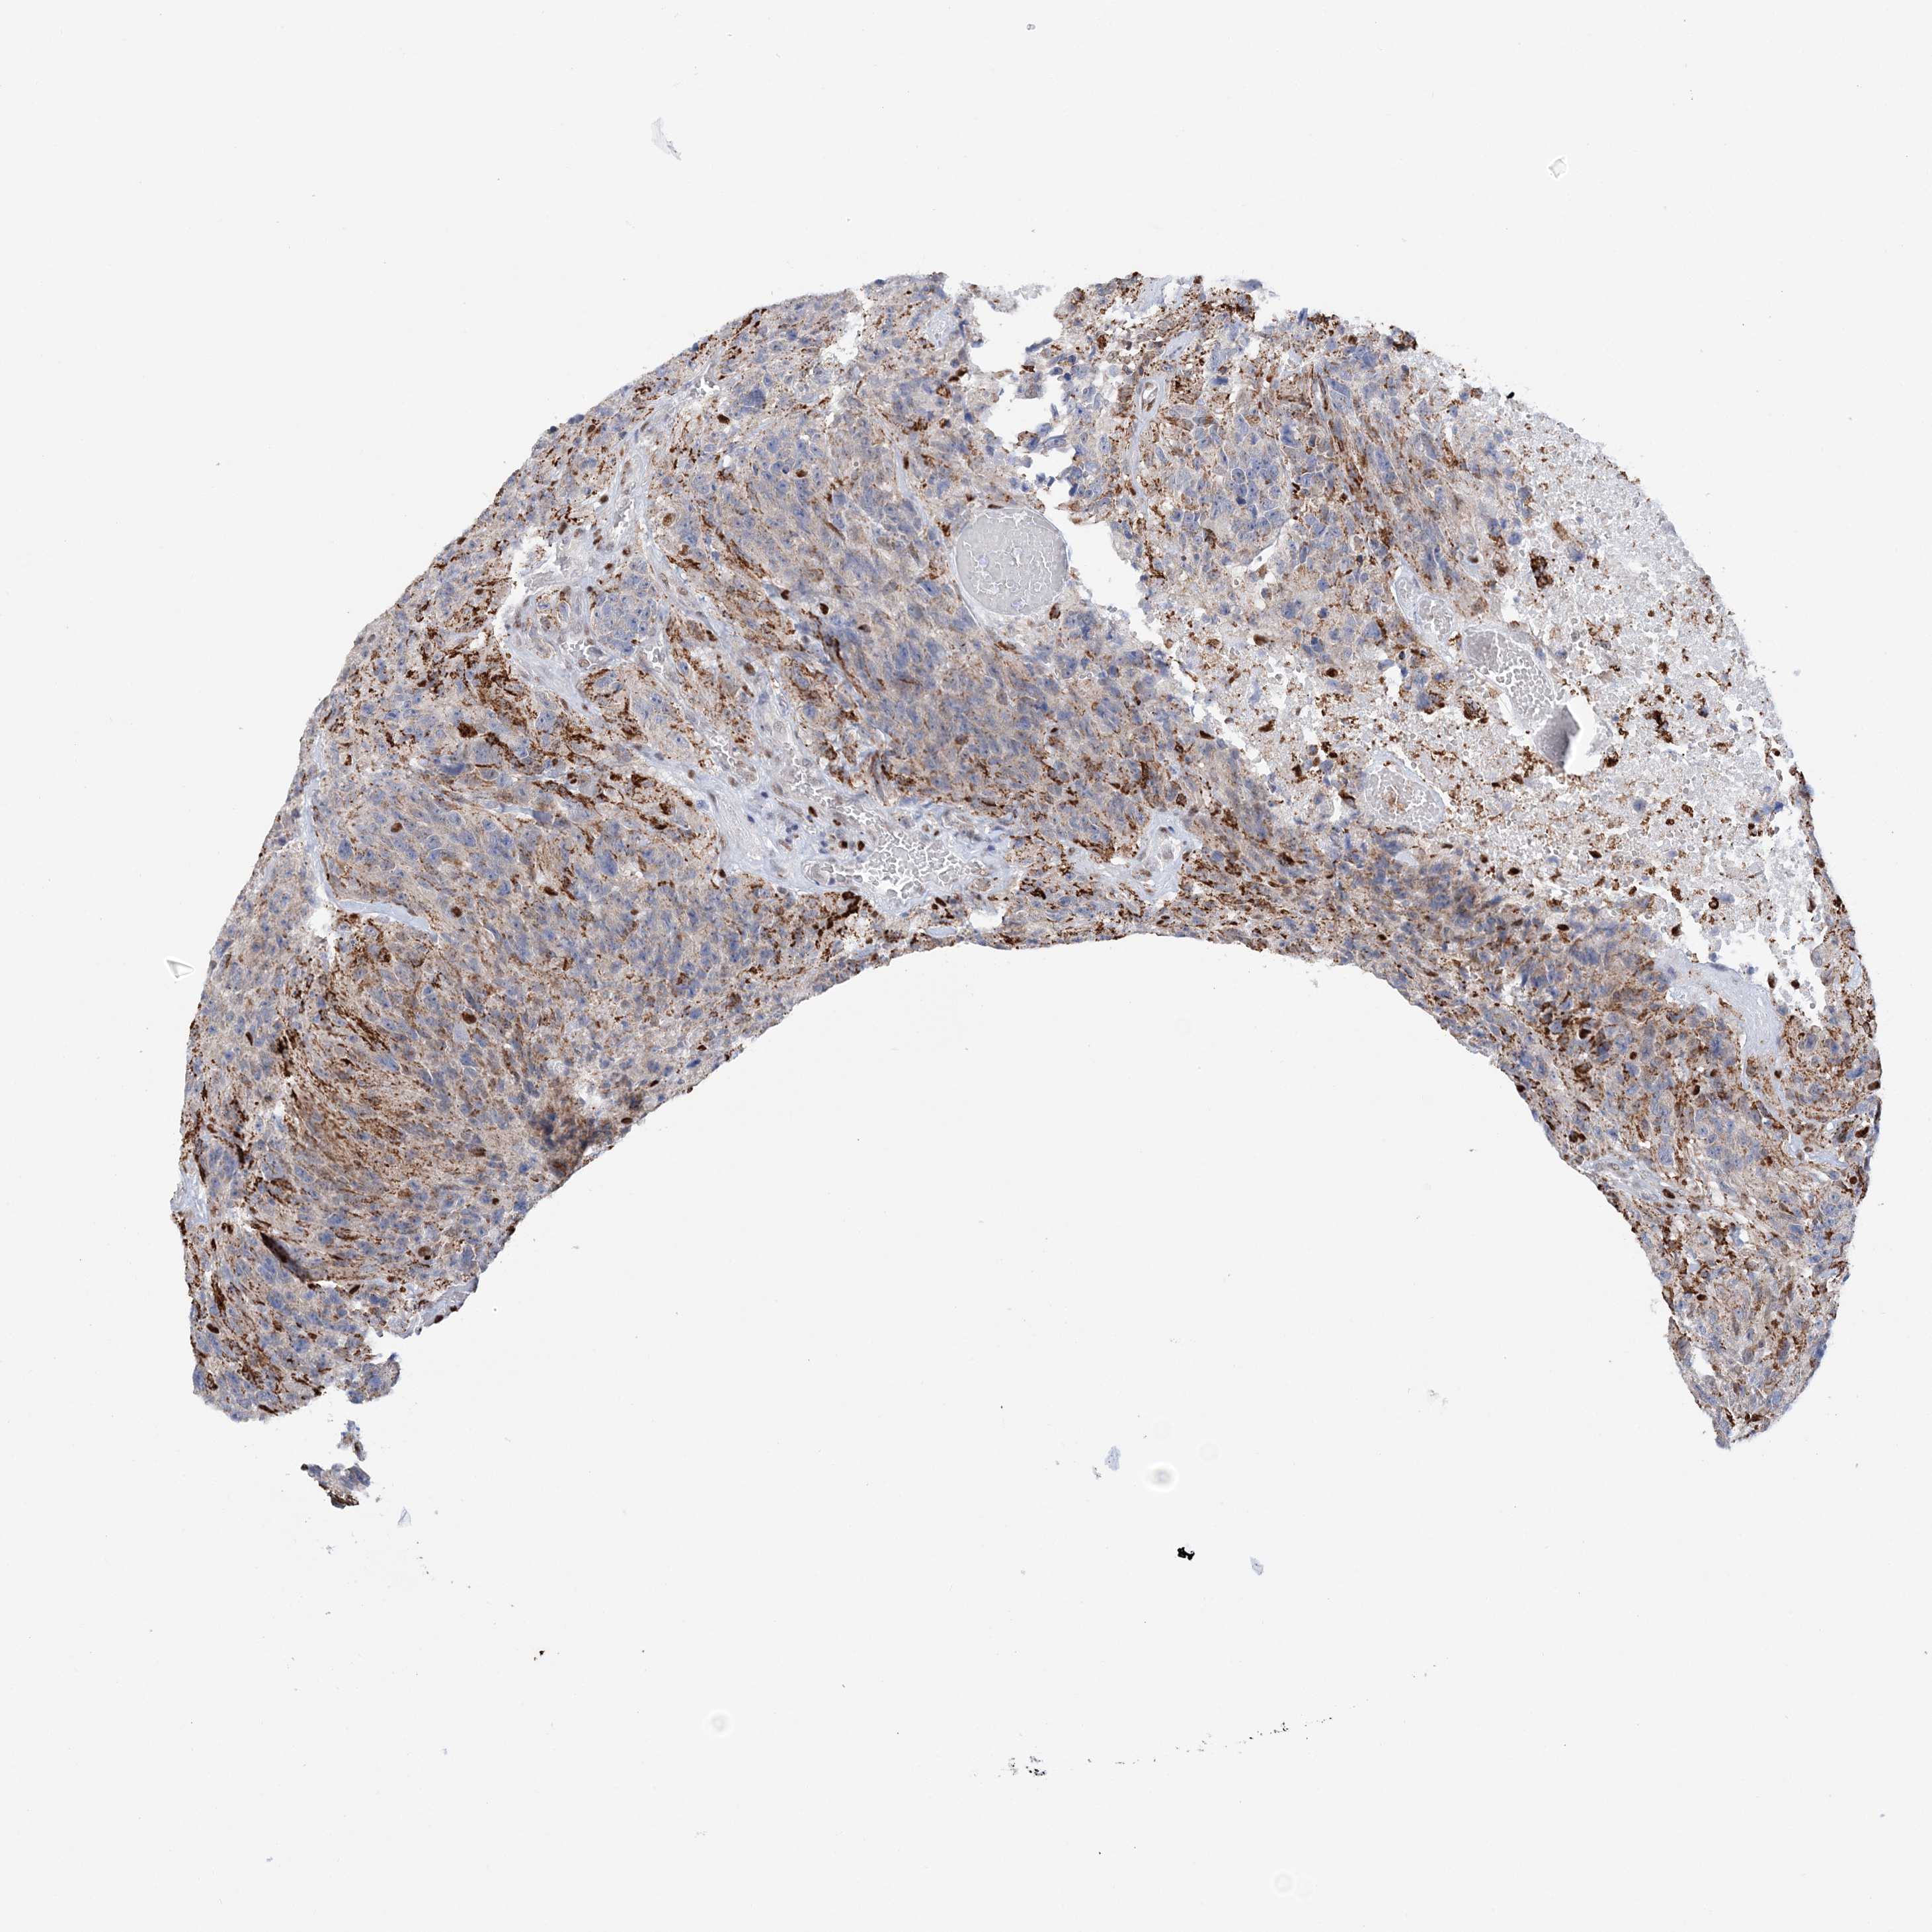

GLIOMA - Protein expressioni

A mouse-over function shows sample information and annotation data. Click on an image to view it in a full screen mode. Samples can be filtered based on level of antibody staining by selecting one or several of the following categories: high, medium, low and not detected. The assay and annotation is described here.

Note that samples used for immunohistochemistry by the Human Protein Atlas do not correspond to samples in the TCGA dataset.

Antibody stainingi

Antibody staining in the annotated cell types in the current human tissue is reported as not detected, low, medium, or high, based on conventional immunohistochemistry profiling in selected tissues. This score is based on the combination of the staining intensity and fraction of stained cells.

Each image is clickable and will lead to virtual microscopy that enables deeper exploration of all samples and also displays staining intensity scores, fraction scores and subcellular localization as well as patient and tissue information for each sample.

Antibody HPA036999

Antibody HPA041289

Staining

High

Medium

Low

Not detected

Intensity

Strong

Moderate

Weak

Negative

Quantity

>75%

75%-25%

<25%

None

Location

Nuclear

Cytoplasmic/membranous

Cytoplasmic/membranous,nuclear

Glioma, malignant, High grade

Glioma, malignant, Low grade

Glioblastoma, NOS